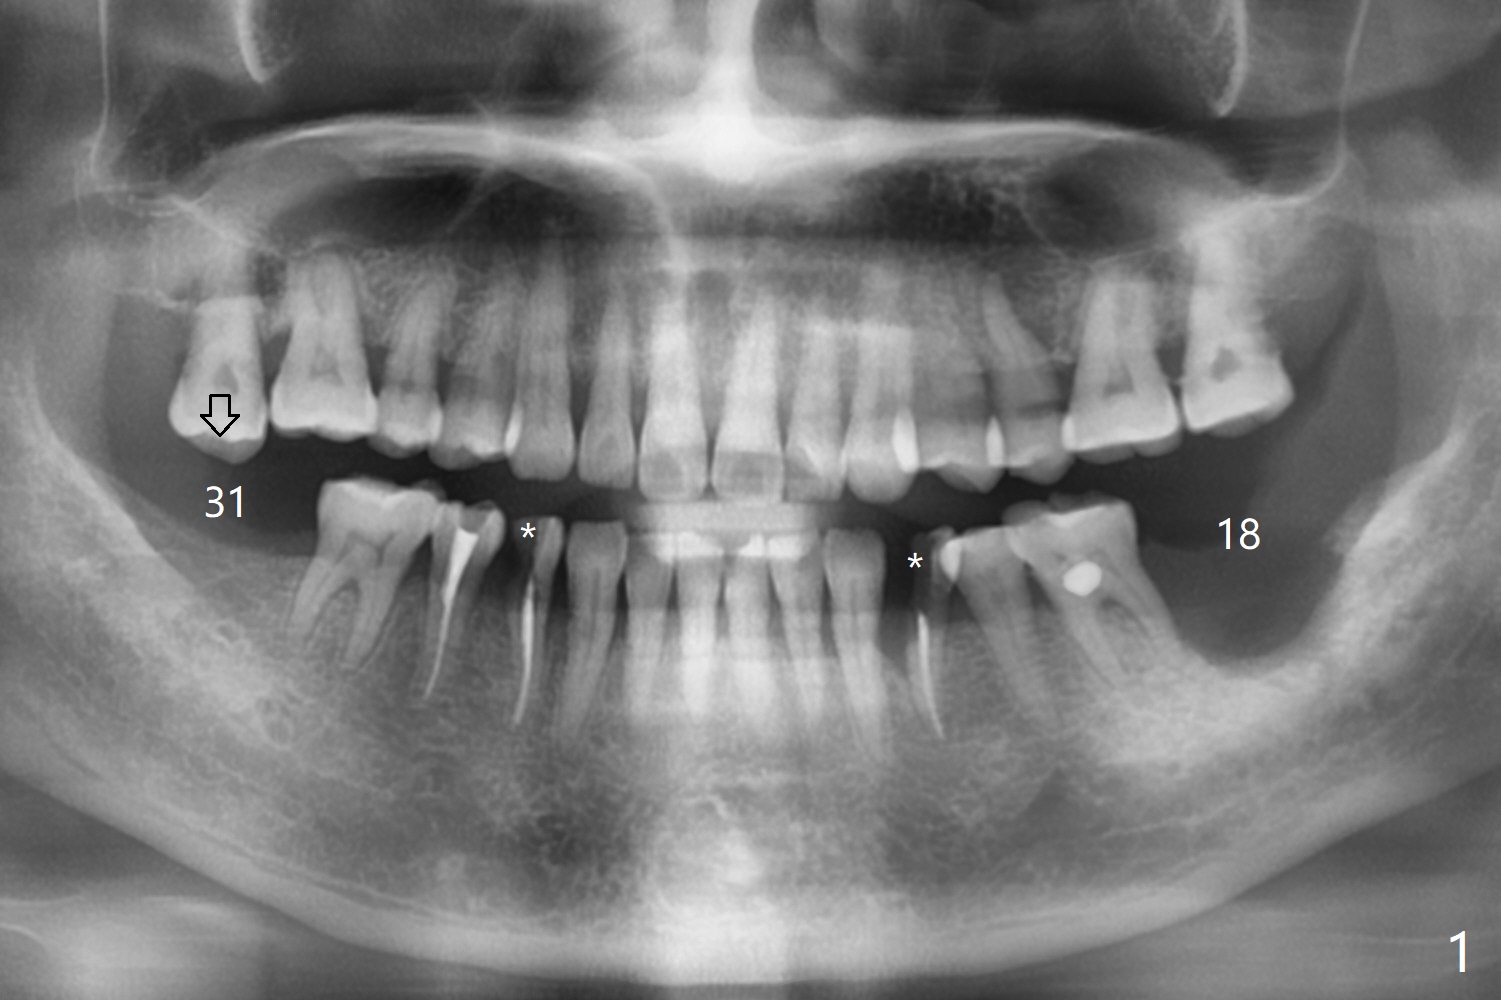

To increase bone density, use a large 8/9 mm trephine bur to harvest ramus block graft on the right with depth of 3 mm (Fig.4 red circle) after SRP in the lower arch and transfer to #18 socket (Fig.3 pink), fixed in place with a screw (probably 6 or 8 mm tenting one, yellow) after filling the socket with particulate bone graft (Vanilla, white circle).